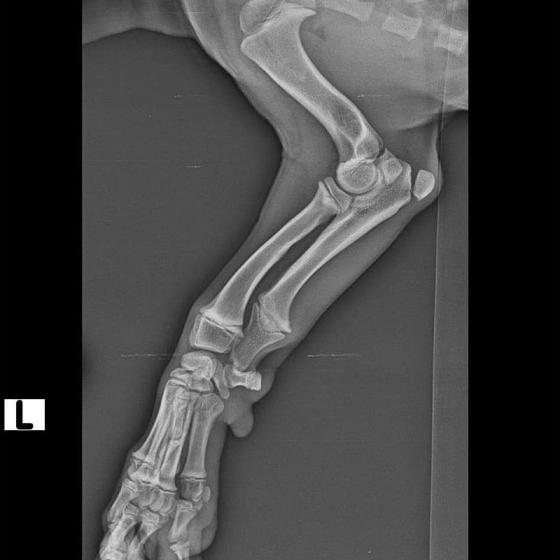

Odoberal sa od drogovo závislých asociálov, ktorý boli vysťahovaný z domu. Ihly, striekačky, ľudské výkaly, rôzne neidentifikovateľné zvratky, špinavé oblečenie, použité kondómy - to všetko nahádzané na jednu kopu v obývačke, kde Pluto so svojou maminkou Miou žili. :( Nevieme ako sa to stalo, kto mu ublížil, ale Pluto má prestrelenú prednú nohu! Viete si predstaviť toho psychicky narušeného človeka, ktorý strieľa na malé bezbranné šteniatko? V dôsledku strelnej rany má doslova rozdrvenú lakťovú kosť. Mali sme veľké obavy, že o nožičku príde, ale MVDr. Vatolík s teamom veterinárnej kliniky Sibra centrum opäť urobil zázrak a malému nožičku napravil a prognóza je viac než dobrá. Čaká ho ešte dlhá cesta k zotaveniu, ale je to odvážny a statočný bojovník. Nechceme si ani len predstaviť čím všetkým si tie zvieratká muesli prejsť, a kto vie koľko ich pôvodne bolo.. Nikto nevie ako a kde skončili Plutovi súrodenci...